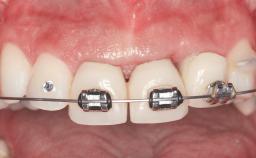

Replacement of Teeth 12 and 13 with Tissue-Level Implants

In 2001, a 48-year-old woman presented at a dental clinic with a failing fixed partial denture spanning from teeth 13 to 21. She was experiencing pain upon function, tenderness to palpation facial to tooth 13, and severe mobility of the prosthesis. Radiographic and clinical assessment revealed a subcrestal fracture of tooth 13, making its restoration unlikely. It was determined by the clinician that the tooth needed to be extracted prior to proceeding any further with dental care. After the extraction, the patient lost confidence in the progression of her treatment and sought consultation at the Center for Implant Dentistry. At her consultation visit in our clinic, an extra- and intraoral clinical examination revealed a medium lip line at full smile and an edentulous area spanning from 13 to 12 with both vertical and horizontal deficits in hard and soft tissue.